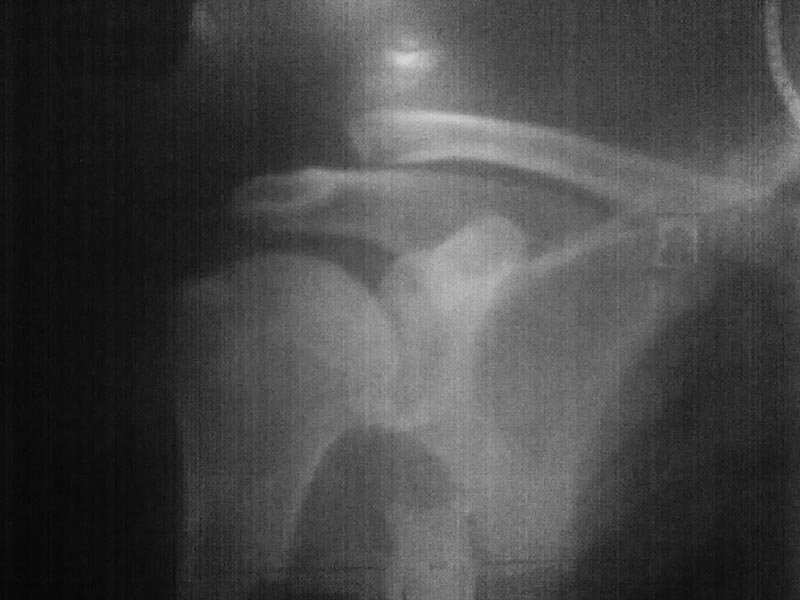

Здесь снимки, которые показывают направление стержня, а также идею репозиции вытяжением. На рентгенопроницаемых столах имеется возможность установить дополнительную раму, где по желанию можно увеличить или уменьшить высоту угла вытяжения. Для репозиции таза больной в положение на спине, стержень для вытяжения остается во время операции. Система подойдет для тракции головки бедра из вертлужной впадины, и для этого стерильная веревка и Synthes Universal Chuck with T-Handle.

Двухстороннее повреждение крестца и травматическая ампутация бедра, где неопытной бригадой дежурантов установлен верхний наружный фиксатор для стабилизации. На третий день ревизия на более стабильный, и окончательная фиксация. Первые снимки после стабилизации таза, и другие, где показаны (параллельные) правильная установка на AIIS т.е на месте прикрепления прямой мышцы бедра. Ампутация закончена костно пластическим методом.